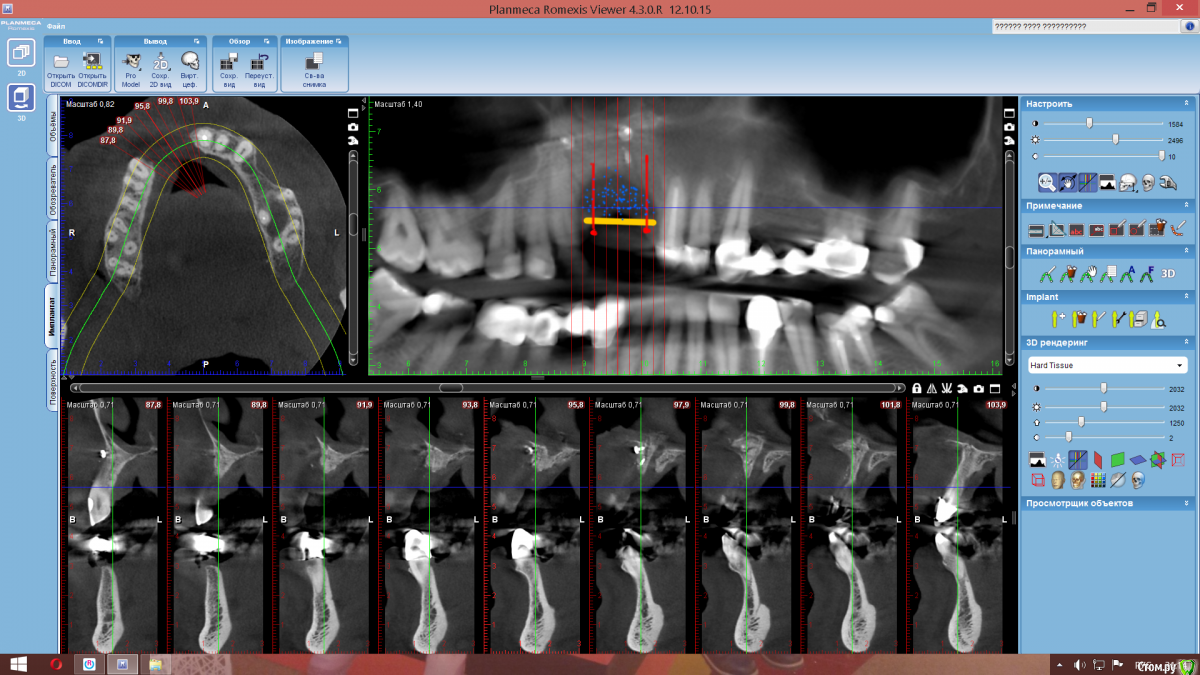

Nazim_NV86 Опубликовано 3 апреля, 2017 Поделиться Опубликовано 3 апреля, 2017 Доброе время суток коллеги. Вот такой вот вертикальный дефект. Была неудачная попытка костной пластики. Собираюсь делать ламинами, но хотел бы почитать ваши рекомендации, а возможно и ссылки на похожие операции. Ссылка на комментарий

kamranchick Опубликовано 4 апреля, 2017 Поделиться Опубликовано 4 апреля, 2017 (изменено) вы можете заугментировать резцовый канал, он у вас довольно таки широкий, получить там кость, и в будущем заанугулировать имлантат при желании, вот так можно зафиксировать блок, держится очень крепко, проблема чтобы смогли ушить и сделать мобилизационэ))) Изменено 4 апреля, 2017 пользователем kamranchick Ссылка на комментарий

kamranchick Опубликовано 4 апреля, 2017 Поделиться Опубликовано 4 апреля, 2017 Доброе время суток коллеги. Вот такой вот вертикальный дефект. Была неудачная попытка костной пластики. Собираюсь делать ламинами, но хотел бы почитать ваши рекомендации, а возможно и ссылки на похожие операции. Ссылка на комментарий